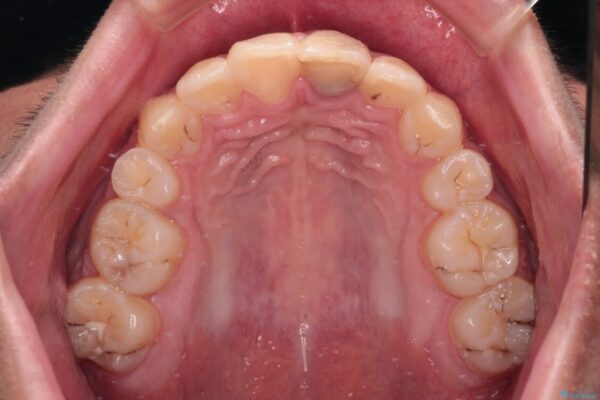

治療前

• 膨らんだ口元 ワイヤー装置での抜歯矯正 治療前画像